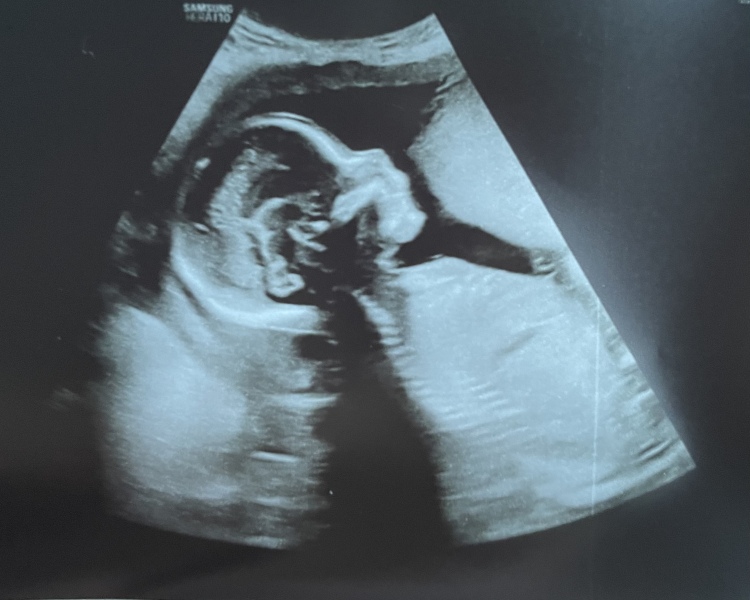

@xalexandra so it didn’t really go to plan sadly. She’s okay but measuring very small. Especially her head, so back on Thursday for a re-scan.

then a double whammy, my placenta is covering my cervix. Lots of extra scans booked in and a whole lot of extra worry 😞

xalexandra · 08/01/2023 17:48

@Sprinklerainbows measurements can be all

Over the place I've heard? Did they seem concerned?

Does that mean c section on the cards? I've seen so many people say how much chilled the C section was compared to a vaginal birth!

A lovely scan pic though 🤍 I guess at this stage, especially the 20 week scan they have to be extra cautious on everything and double check everything - maybe she's just a small bubba ✨

Sprinklerainbows · 08/01/2023 18:52

@xalexandra Yes! I’m trying not to worry TOO much until the rescan. She’s measuring about 2 weeks behind, so the absolute lowest percentile. If she’s even 0.1 below next week, it’s a fetal medicine referral. Hoping it’s a bad scanning error though 😅

Yes it’s a bit scary, you have to call 999 if you bleed, there’s a pretty big risk of haemorrhage and pre term birth via emergency section. I’m worried but also most do move! I had an amazing, quick labour with my son so I’m really really hoping to get to do it one last time! But as long as she’s here safe that’s all I care about

aw thank you! They didn’t charge me for it because she felt sorry for me 😅 xx